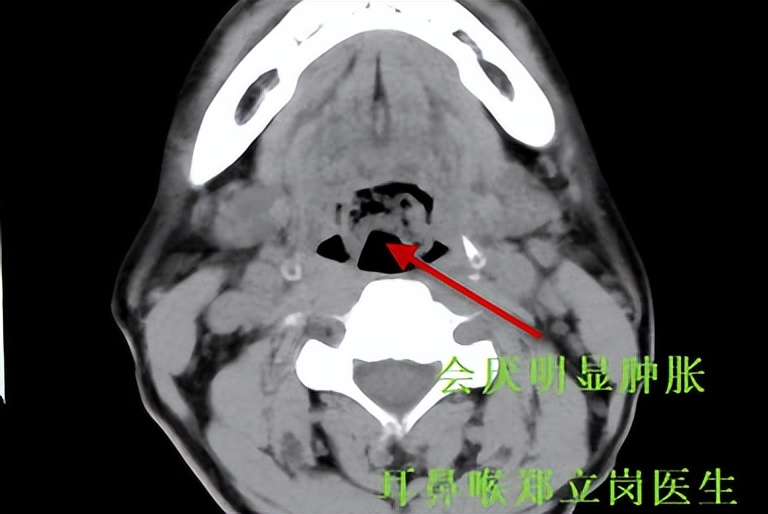

做了个CT检查,会厌明显的肿胀,如下图所示。